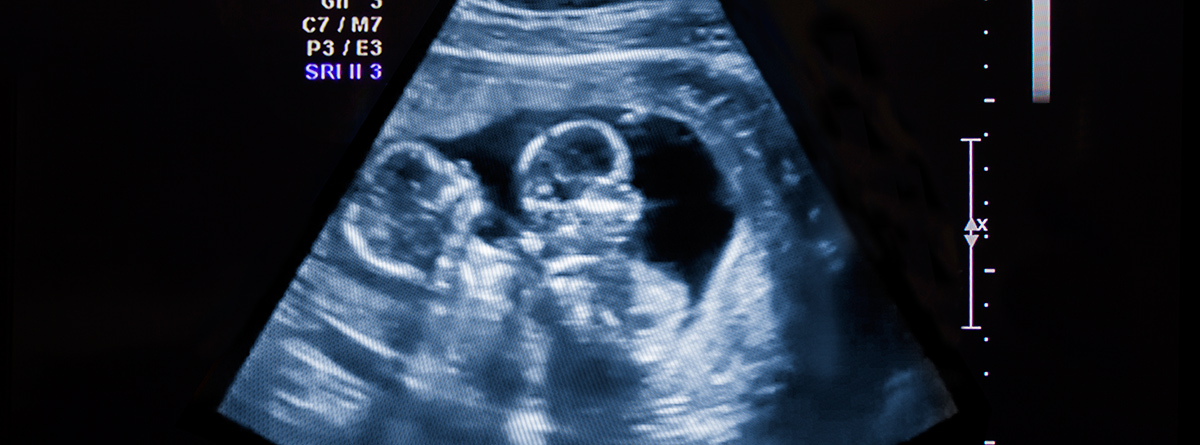

¿Tiene más riesgo un embarazo gemelar?

¿Tiene más riesgos un embarazo gemelar?